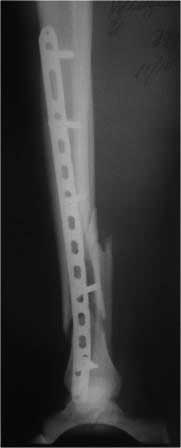

Королев Максим 05 Ноябрь 2012, 11:27

Здравствуйте,

Отвечаю.

Фиксатор- DMT synthes

Пол мужской

возраст 31 год

Вес 105 кг

Конституция нормостеник

Наши возможности: штифты, винты, пластины (различных фирм) от Zimmer до "Казань". ЭОП в наличии.

Нижний винт в диафизе? - возможно.

Винты в диафизе блокируемые.

Винт в переломе как и первичная репозиция - наша ошибка.

Насчет состояния мягких тканей после MIPPO, решили дать передышку себе и пациенту. (лечился по квотной программе)

Снимки лучшего качества, в т.ч. первичные, отправил.

первичные снимки b послеоперационные качеством получше.